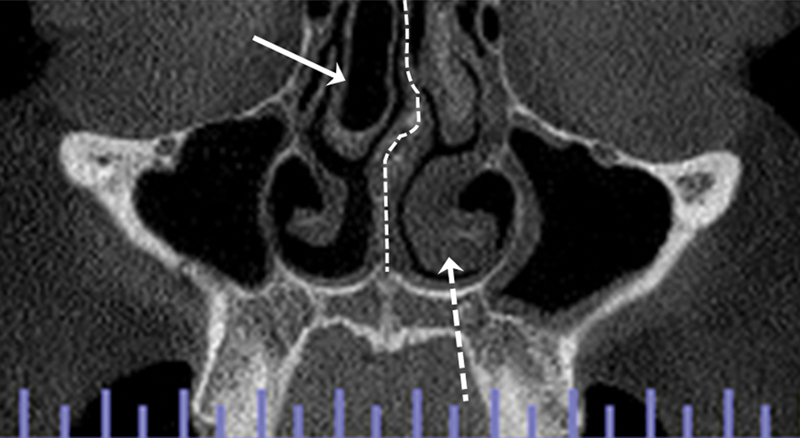

Introduction  In the literature, there is divergence about the relationship between anatomical variations of the turbinates and nasal septum (NS) and alterations in the maxillary sinus (MS) mucosa. Objective  To determine, through cone-beam computed tomography (CBCT) images of Brazilian individuals, the prevalence and relationship of anatomical variations of the turbinates and NS with alterations in the mucosa of the MS, as well as to analyze the relationships of these variables with demographic data. Methods  The present cross-sectional study involved the analysis of 120 CBCT scans using the i-CAT Vision software, conducted by 2 calibrated examiners. The MS, lower and medium turbinates, and NS were evaluated. Data on gender, age, and the side affected by anatomical variation were also collected. The intra- and interexaminer agreements were assessed using Kappa indices. The association was analyzed using the Chi-squared or Fisher exact tests, and measured by the Phi, Cramer V, or Kendall Tau-C values. Results  Most patients presented partial opacification of the MS (89.2%), inferior turbinate hypertrophy (TH) (60.8%), and NS deviation (85%). There were no cases of inferior concha bullosa (CB), while the prevalence of middle CB was of 20%. Variation in the turbinates, CB, and NS were not significantly related to changes in the MS mucosa. Conclusion  We can conclude that, in the evaluated sample, there was no significant associations involving the studied variables.